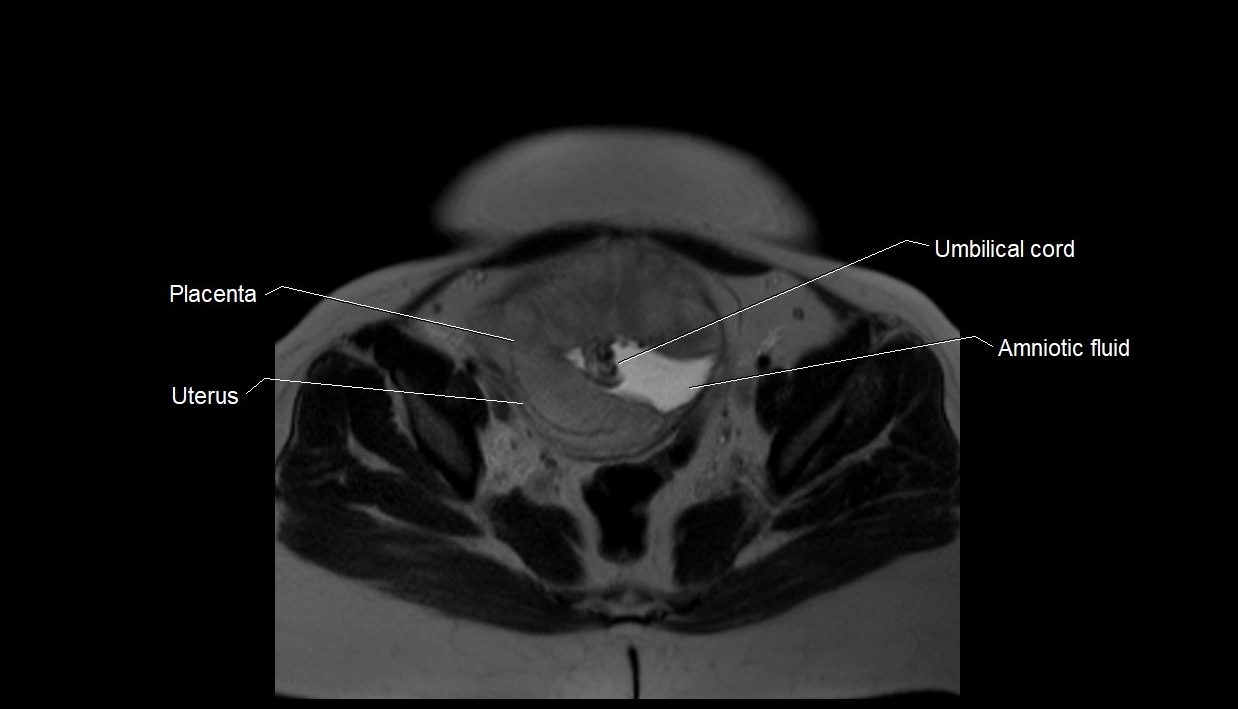

MRI Appearance

T2 HASTE (T2 GRE):

• Amniotic fluid shows very bright hyperintense signal

• Provides natural contrast against fetus and placenta

• Small particles (vernix) may appear as scattered hypointense foci within bright fluid

MRI image

image